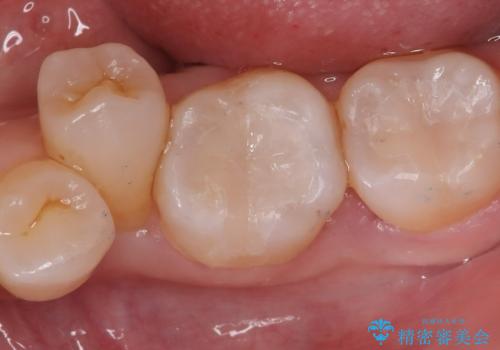

【セラミックインレー】口の中の銀の詰め物を白い物に替えたい

下顎大臼歯部に入っている保険適用のメタルインレーを、適合性と審美性の良いセラミックインレーでのやり替えとなりました。

セラミックインレーセット時はラバーダム防湿を行っています。